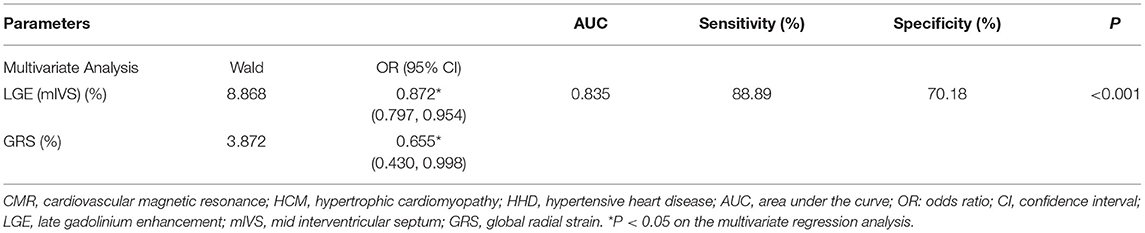

The results of the ROC analysis to discriminate between HCM and HHD are shown in Table 4. GRS (AUC: 0.734, sensitivity: 62.22%, specificity: 75.44%, P < 0.001), GCS (AUC: 0.718, sensitivity: 64.44%, specificity: 71.93%, P < 0.001), and corresponding strain rate could distinguish HCM from HHD. For segmental strain parameters, the AUCs of BRS, BCS, BLS, MRS, and MCS for discriminating between HCM and HHD were 0.781, 0.776, 0.644, 0.711, and 0.697, respectively (all P < 0.001). The torsion cutoff value of > 1.40 differentiated HCM from HHD with a sensitivity of 71.11% and a specificity of 75.44%. The AUC of LGE (mIVS) was 0.735, which was the highest in the global and other segmental LGE analyses (all P < 0.05). Overall, BRS showed the highest diagnostic performance and the value of the AUC was 0.781 (all P < 0.05). On the multivariate regression analysis, the combination model of LGE (mIVS) with GRS obtained the highest AUC value, which was 0.835 with 88.89% sensitivity and 70.18% specificity, respectively (Table 5). DeLong's test showed that the AUC of a combined model of GRS with LGE (mIVS) was higher than those of GRS, GCS, torsion, and LGE (mIVS) (all P < 0.05) (Figure 4).

Table 5. The multivariate logistic regression analysis of CMR parameters for discrimination of patients with HCM and HHD.